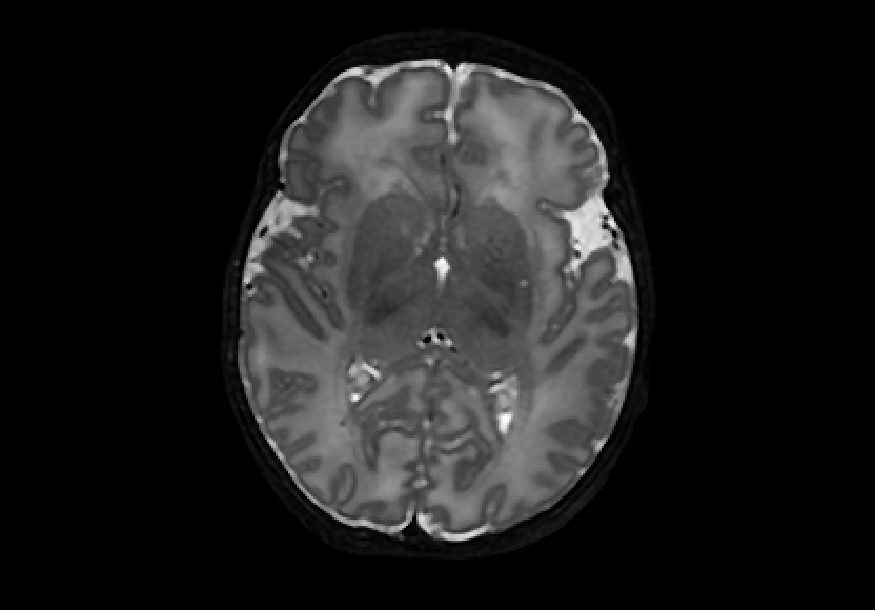

Blur is a rather unique family of MRI artefacts because it can be introduced into a scan after the acquisition stage, such as during post-processing or in the manifestation of pathological conditions [7]; simulating blur textural artefacts was therefore important and relevant for this study. We used the well-established Gaussian blur, which can be produced by continuously applying a Gaussian filter to the image. Different degrees of blurring can be obtained by altering the parameter, where higher values of give blurrier transformations. We employed Gaussian filters from the library scikit-image [10] with = {1, 2, 3, 4, 5} to give five different degrees of Gaussian blurred datasets named gaus01-05, respectively. Figure 2 shows examples of noisy images.